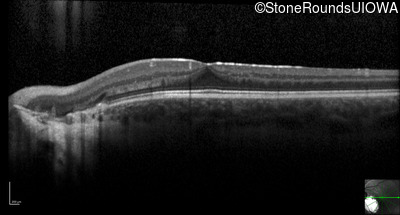

Optical Coherence Tomography - Right - 20/40 +2

Exemplar / OCT Stack